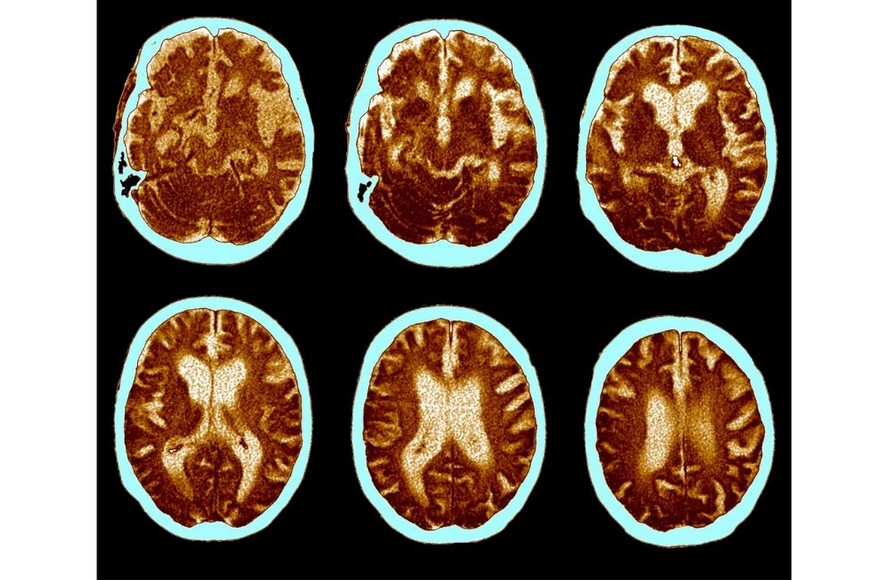

El Alzheimer es un trastorno neurológico que ocasiona la degeneración del cerebro, afectando a las neuronas y generando un deterioro progresivo en el pensamiento y el comportamiento de la persona, lo que eventualmente dificulta su capacidad para vivir de manera independiente.

Esta enfermedad se caracteriza por la acumulación de formas tóxicas de la proteína beta amiloide, la cual desempeña un papel crucial en la transmisión de información en el cerebro, especialmente entre las neuronas.

Esta acumulación provoca daños en la estructura interna de las neuronas, donde la proteína tau juega un papel importante, conduciendo a la degeneración de las células nerviosas. Hasta la fecha, no identificó un único factor que desencadene directamente esta enfermedad y se cree que una variedad de factores, como la edad, la predisposición genética, el entorno, los hábitos alimenticios y el estado de salud general, contribuyen a su desarrollo.